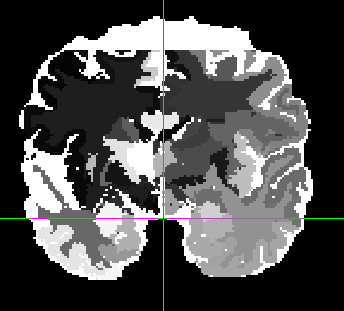

[#4798] HAMMER Labeling Crops Off Top of Brain and Labels it as CSF

Summary: more information HAMMER Labeling Crops Off Top of Brain and Labels it as CSF |

I've been using the original

release of HAMMER since 2007. Recently I decided to try out the

current release of HAMMER. RAVENS and registration work very well.

However, the labeling feature produces the odd artifact that you

see in the pictures. Somehow the top of the brain is cropped off

and set to CSF. This did not happen using the same image and model

using the older release of HAMMER (as seen in the picture).

| File Added | 283: current-hammer.png | 2010-04-22 15:48 | dcb210 |

| File Added | 282: previous-hammer.png | 2010-04-22 15:48 | dcb210 | |